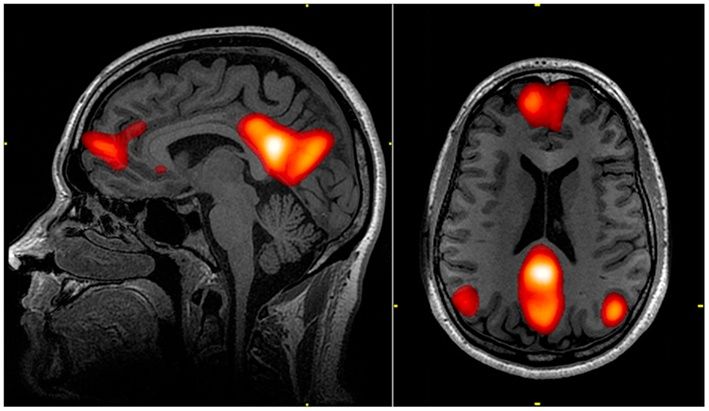

Απεικόνιση του δικτύου προεπιλεγμένης λειτουργίας του εγκεφάλου

John Graner/Wikimedia Commons

Ταυτόχρονα, το δίκτυο προεπιλεγμένης λειτουργίας ενεργοποιείται, μετατοπίζοντας την προσοχή μας προς τις εσωτερικές σκέψεις και την αυτοανασκόπηση. Αυτή είναι μια βασική λειτουργία του δικτύου προεπιλεγμένης λειτουργίας, που αναφέρεται ως ενδοσκόπηση και αποτελεί μια στρατηγική για την αντιμετώπιση της πλήξης.